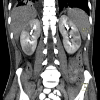

КТ забрюшинного пространства. Исследование забрюшинного пространства путем получения и реконструкции срезов срезов на КТ-сканере. Наиболее важные анатомические структуры расположены в забрюшинном пространстве: почечные и периральные волокна, мочеточники, надпочечники, лимфатические узлы и кровеносные сосуды - эти органы являются основными объектами КТ. При внутривенном введении специальных йодсодержащих препаратов почечные артерии могут быть противопоставлены. Показаниями к забрюшинному КТ могут быть травмы живота и поясничного отдела позвоночника, опухоли почек и надпочечников, гнойные процессы, предполагаемые метастазы в этой области, повреждение лимфатических узлов Забрюшинная КТ может быть независимым диагностическим исследованием или проводиться совместно с КТ брюшной полости.

Забрюшинная томография является высокоинформативным методом диагностики заболеваний внутренних органов, расположенных в забрюшинном пространстве. В сканере используется сканер, оборудованный рентгеновской трубкой и датчиками. Рентгеновская трубка испускает излучение, частично поглощаемое тканями. Датчики обнаруживают изменение излучения, информация передается на компьютер, обрабатывается специальными программами, и моделируется трехмерное изображение области исследования. Компьютерная томография в забрюшинном пространстве позволяет точно диагностировать патологические процессы на ранних стадиях развития, что важно для быстрого выявления различных патологий и проведения адекватного лечения.

КТ забрюшинного пространства выполняется с помощью томографа. Пациент помещается на кушетку в положение на спине, после чего кушетка перемещается к кольцевому аппарату. При контрастировании препарат вводится непосредственно перед процедурой. Во время КТ забрюшинное пространство вокруг тела пациента вращает трубку, испускающую рентгеновские лучи, которые поглощаются тканями. Излучение регистрируется датчиками, информация передается на компьютер. Во время сканирования пациент должен оставаться неподвижным, чтобы изображения были максимально четкими. Продолжительность томографического исследования - не более 5 минут; с использованием контрастного увеличения продолжительность процедуры может быть увеличена до получаса.

Получите результаты КТ забрюшинного пространства в тот же день. При изучении изображений рентгенолог делает заключение о выявленных структурных нарушениях исследуемых структур, наличии воспалительных изменений и гнойных очагов. Также можно определить новообразования, установить их точное местоположение, размер и распространенность. После проведения забрюшинной компьютерной томографии пациенту предоставляется письменное мнение и фотографии на бумаге или на цифровом носителе. Затем пациент должен обратиться к лечащему врачу для точного диагноза и определения последующей стратегии лечения.